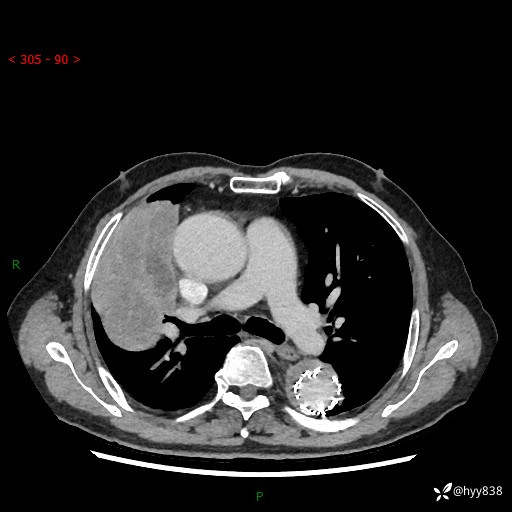

胸部CT平扫